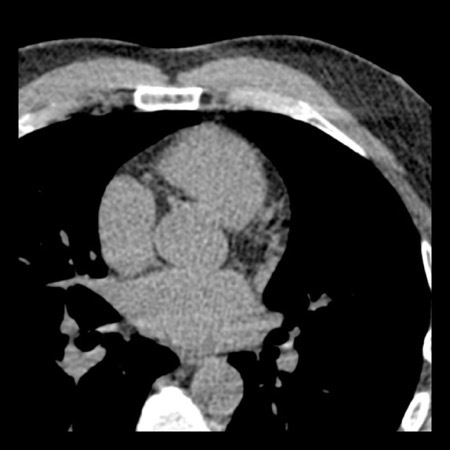

case 1 – CAD-RADS 2/P1

First, scroll through the scan.

Not all images are included. Some images without any abnormalities are skipped

from the series.

How would you describe the findings on the coronary CTA?

The findings are:

- Agatston score of

this patient was 14 (P1). Please, also note the calcification of the aortic valve. - Some partially

calcified and calcified plaques are present in the LAD with mild stenosis

(25-49%). - Calcified-plaque in

the LCX causing minimal stenosis (<25%). - Non-calcified

plaque in the distal RCA causing minimal stenosis (<25%). - This patient classifies

as CAD-RADS 2/P1, which means no further workup is needed.